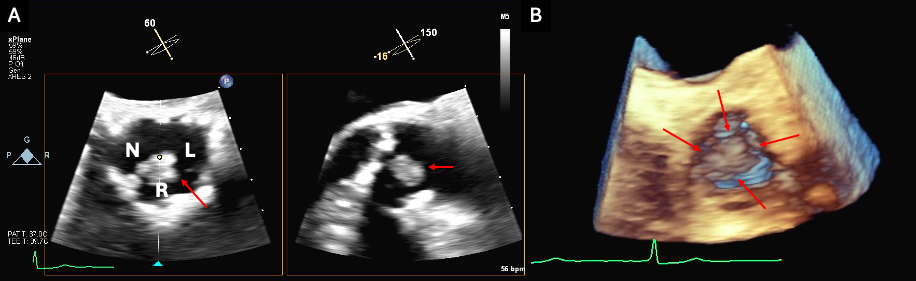

A 93-year-old woman with symptomatic severe aortic stenosis and normal biventricular function was referred for transcatheter aortic valve replacement (TAVR) evaluation (Figure 1A, Video 1). Cardiac computed tomography revealed safe coronary heights and multiple large calcified mobile mass-like structures attached to the aortic valve (AV), confirmed also by transesophageal echocardiography, which were thought to be prominent Lambl’s excrescences. (Figure 2, Videos 2 and 3). Coronary angiography found a 50% to 60% calcified lesion in the proximal right coronary artery (RCA) (Figure 3A, Video 4). Aortic arch vessels were deemed not suitable for cerebral embolic protection.

Transfemoral TAVR with 26-mm Evolut FX valve (Medtronic) was successfully performed. Commissural misalignment was noted (Figure 4). The implant depth was 4 mm and RCA flow was present (Video 5). Transthoracic echocardiography (TTE) showed no paravalvular regurgitation, a mean gradient of 3 mm Hg, and normal biventricular function (Video 6). The patient was pacing-dependent after valve deployment. Two hours afterwards, the patient became hypotensive and developed polymorphic ventricular tachycardia requiring electrical cardioversion. TTE revealed right ventricular dilation and severe dysfunction (Figure 1B, Video 7). An intra-aortic balloon pump was placed and repeat coronary angiography found a total occlusion of the RCA ostium (Figure 3B, Video 8), which was successfully treated by percutaneous coronary intervention with 2 drug-eluting stents (Figure 3C, Video 9). The patient clinically improved and was safely discharged home on post-op day 10.

Coronary obstruction is a rare, life-threatening (> 40% 30-day mortality rate) complication of TAVR.1 Cardiac computed tomography (CCT) represents the gold standard to identify predictors of obstruction. Mechanisms responsible for RCA obstruction in this case include aortic valve mass embolization or impingement with ostial effacement, commissural misalignment (as it may impact coronary access in supra-annular self-expanding valves2,3) or a combination. Echocardiography is crucial for early identification and rapid management of cardiac dysfunction due to subacute coronary obstruction after TAVR.